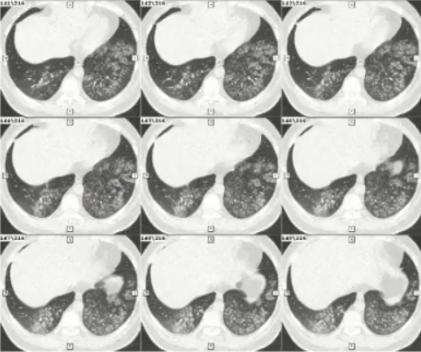

病例1

女性,15岁,既往曾行脊柱侧弯矫形术。因发热、咳嗽、咳黄痰1周入院。

发病后2天起予头孢曲松+阿奇霉素治疗至入院当日,日最高体温从39.9℃降至38.3℃,但发热、咳嗽、咳黄痰无进一步好转。

血常规检测:

• 发热第3天:WBC 5.34×109/L,N 0.659,CRP 1.063mg/dl

• 发热第7天:WBC 4.07×109/L,N 0.691,CRP 1.547mg/dl

CK 357.5 U/L,LDH 277.1 U/L

图1 患者的影像学以实变为主